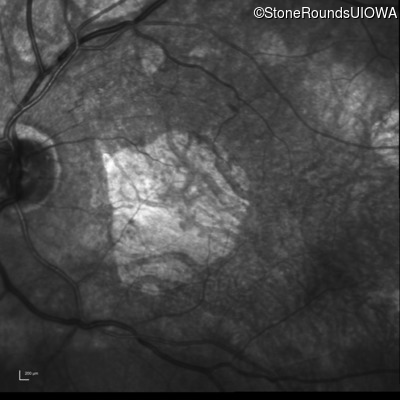

Infrared Fundus Photograph - Right - 20/100

Exemplar

Infrared Fundus Photograph - Left - 20/100